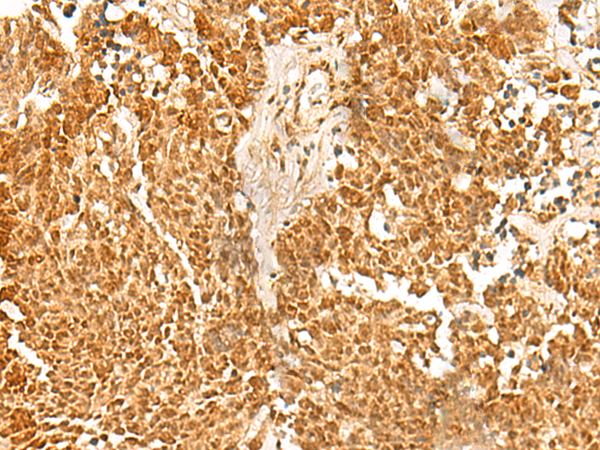

The image is immunohistochemistry of paraffin-embedded Human lung cancer tissue using P03036(ZNRD2 Antibody) at dilution 1/50. (Original magnification: ×200) |

The image is immunohistochemistry of paraffin-embedded Human prostate cancer tissue using P03036(ZNRD2 Antibody) at dilution 1/50. (Original magnification: ×200) |